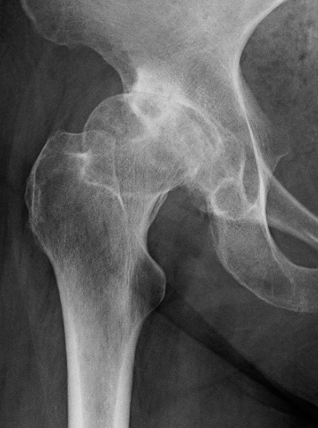

Crowe Classification

| Crowe Type | Definition |

|---|---|

| I | Subluxation < 50% vertical diameter femoral head |

| II | Subluxation 50 - 75% vertical diameter femoral head |

| III | Subluxation 75 - 100% vertical diameter femoral head |

| IV | Proximal migration of > 100% vertical diameter femoral head |

Crowe I

Crowe II

Crowe III

Crowe IV